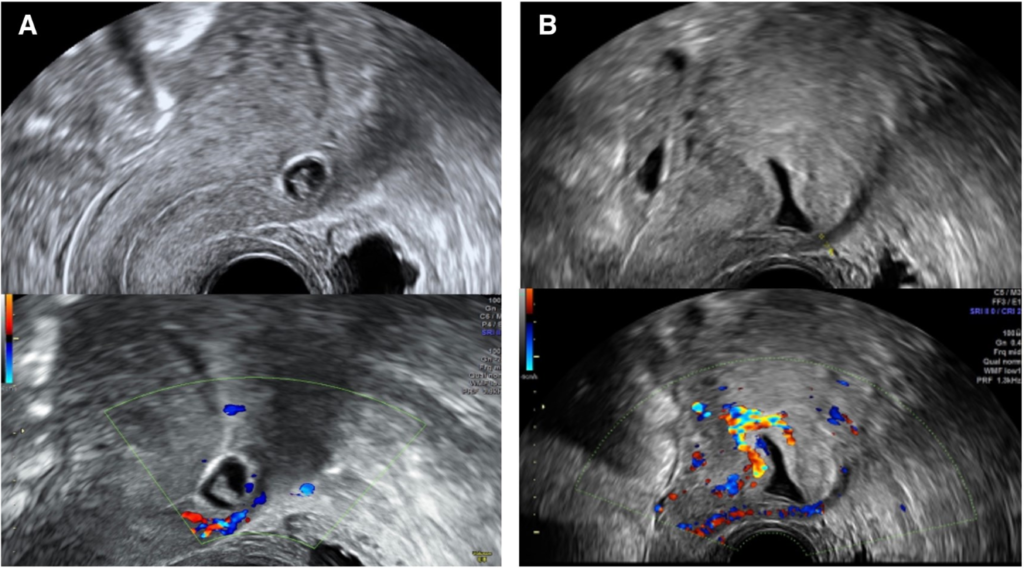

Ektopična trudnoća nastaje kada se gestacija razvija potpuno ili delimično izvan endometrijalne šupljine. Iako su tubarne implantacije najčešći i klinički dobro poznat oblik bolesti, atipične lokalizacije i parcijalne ektopične trudnoće predstavljaju značajan dijagnostički izazov. Kod pacijentkinja sa progresivnom trudnoćom posebno je važno postaviti sigurnu dijagnozu, jer najteža dijagnostička greška može biti nenamerni prekid normalne eutopične trudnoće.

Izbor između ekspektativnog pristupa, koji je kod hemodinamski stabilnih pacijentkinja često adekvatan, i aktivne intervencije zavisi od precizne procene veličine, lokalizacije i vaskularizacije mesta implantacije. Pored neposrednog kliničkog zbrinjavanja, važno je i individualno savetovanje o riziku ponovne ektopične trudnoće, kao i prepoznavanje mogućih psiholoških posledica koje ovaj događaj može imati za pacijentkinju.